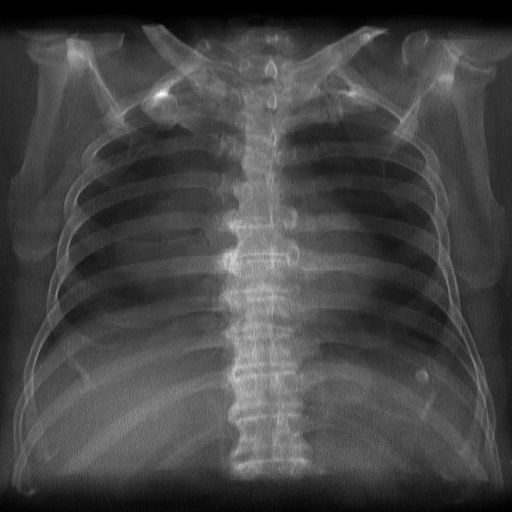

Figure 3 below presents a synthesized DRR generated from a NIfTI volume, where features such as cardiomegaly are prominently displayed. Additionally, other DRR images clearly show signs of consolidation and central bronchiectasis. However, it is important to note that the accompanying text reports were atypical and translated by the authors of the CT-RATE dataset from another language (Turkish) into English, which may affect their readability and clarity.

DRR Image

Labels: {0,0,1,1,0,0,0,0,1,0,0,0,0,0,0,0,0,0}

Findings: Trachea, both main bronchi are open. Heart size increased. Pericardial effusion reaching 2 cm in its thickest part is observed in the pericardial area. Evaluation of mediastinal vascular structures is suboptimal because the examination is unenhanced. As far as can be observed, mediastinal vascular structures were evaluated as normal. Thoracic esophagus calibration was normal and no significant tumoral wall thickening was detected. No lymphadenopathy was detected in the mediastinal area in pathological size and appearance. When examined in the lung parenchyma window; Linear atelectasis areas are observed in the posterobasal sections of both lungs. The upper abdominal organs included in the examination have a natural appearance. Degenerative changes are observed in the bones. No fracture, lytic or destructive lesion was observed. There are extensive osteophytic taperings at the anterior vertebral corners and tend to coalesce.

\cprotectvalid_94_a_2.nii.gz|. The binary labels are in the following order: Medical material, Arterial wall calcification, Cardiomegaly, Pericardial effusion, Coronary artery wall calcification, Hiatal hernia, Lymphadenopathy, Emphysema, Atelectasis, Lung nodule, Lung opacity, Pulmonary fibrotic sequela, Pleural effusion, Mosaic attenuation pattern, Peribronchial thickening, Consolidation, Bronchiectasis, and Interlobular septal thickening.